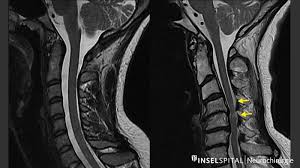

Schmerzen im bein nach spinalkanalstenose op. Starke Schmerzen im Bereich der Beine und auch Rücken sind ebenfalls häufig. Die klassische spinale Stenose äussert sich in Schmerzen in einem oder beiden Beinen die nach einer bestimmten Gehstrecke oder Zeit im Stehen auftreten. In einigen Fällen ist eine OP unvermeidlich.

Die wichtigsten Symptome einer Spinalkanalstenose sind belastungsabhängige Rückenschmerzen und Beinschmerzen hauptsächlich beim Gehen Stehen und. Bei einer Spinalkanalstenose kommt es zu Schmerzen im Bein beim Gehen Tipps zur Vorbeugung und Selbsthilfe alles zu Symptomen. Meine Schmerzen die in die Beine ausstrahlten waren sofort nach der OP weg.

Wenn Schmerzen im Bein sehr gefährlich sind. Die Belastungsfähigkeit ist herabgesetzt. Kreuzschmerzen und ein Ausstrahlen dieser Schmerzen in die Beine sind Symptome einer Spinalkanalstenose.